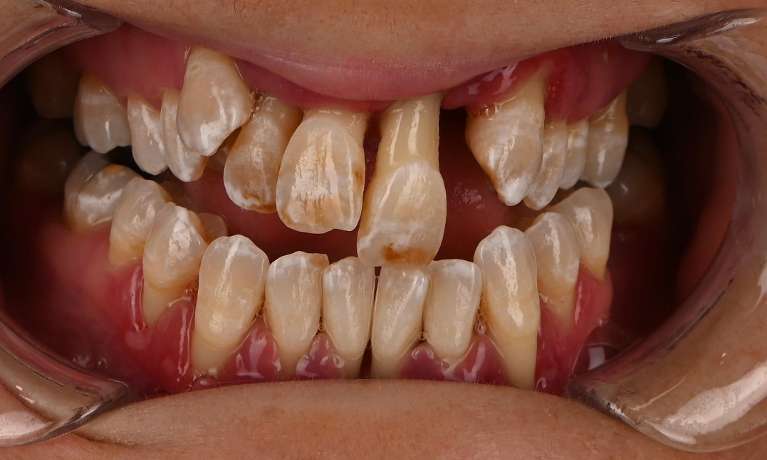

full mouth rehabilitation before and after in warners bayFull mouth rehabilitation can restore and improve the function and wellness of your teeth, gums and overall smile. Ideal candidates for full mouth rehabilitation are those who have several dental concerns that require significant repair or replacement.

Common concerns include:

• Multiple missing teeth

• Severely decayed teeth

• Severely damaged teeth like cracks, chips and wear

• Old or failing dental restorations like crowns or fillings

• Advanced gum disease

• Deep discolouration or staining

• Jaw and bite misalignment and discomfort